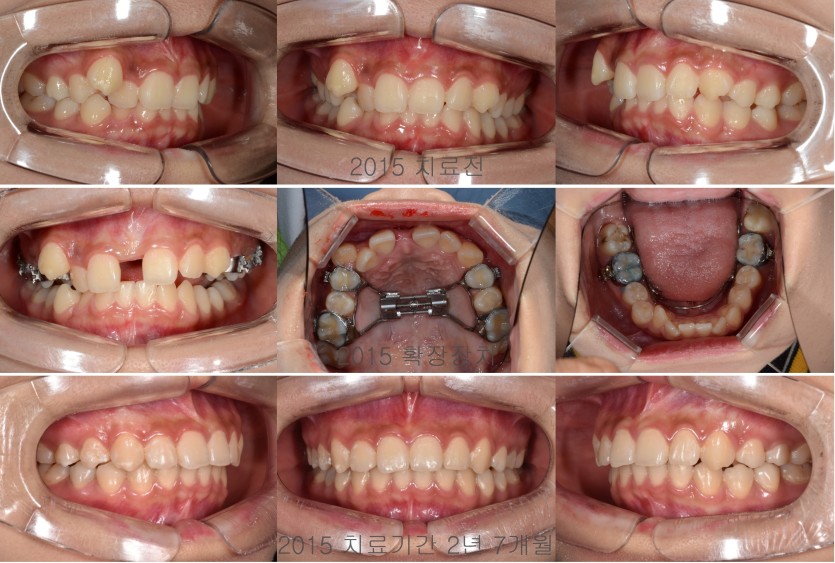

상악을 급속확장하여 덧니 배열공간을 확보한 경우 129회

상악 우측 송곳니의 배열공간이 상당히 부족한 덧니였지만 소구치를 발치하지 않고

상악을 급속확장하는 장치를 이용해서 상악 골격을 확장하면서 덧니를 배열할 수 있습니다.

덧니를 비발치 확장의 방법으로 해결하기 위해서는 안모의 평가, 치조골의 평가, 배열을 위해 필요한 공간의 분석등이 꼼꼼히 이뤄져야 합니다.